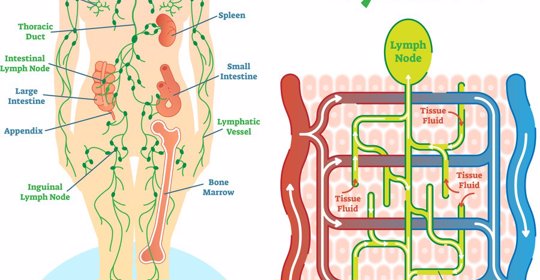

口渴感喪失:自律神經失調的處理方法

本文介紹了自律神經失調所致口苦的處理措施。若症狀由自律神經失調引起,可嘗試生活方式調整、心理行為療法、營養補充、針灸治療等非藥物方法來改善情況。若上述措施無效或症狀加重,應及時尋求醫療幫助。